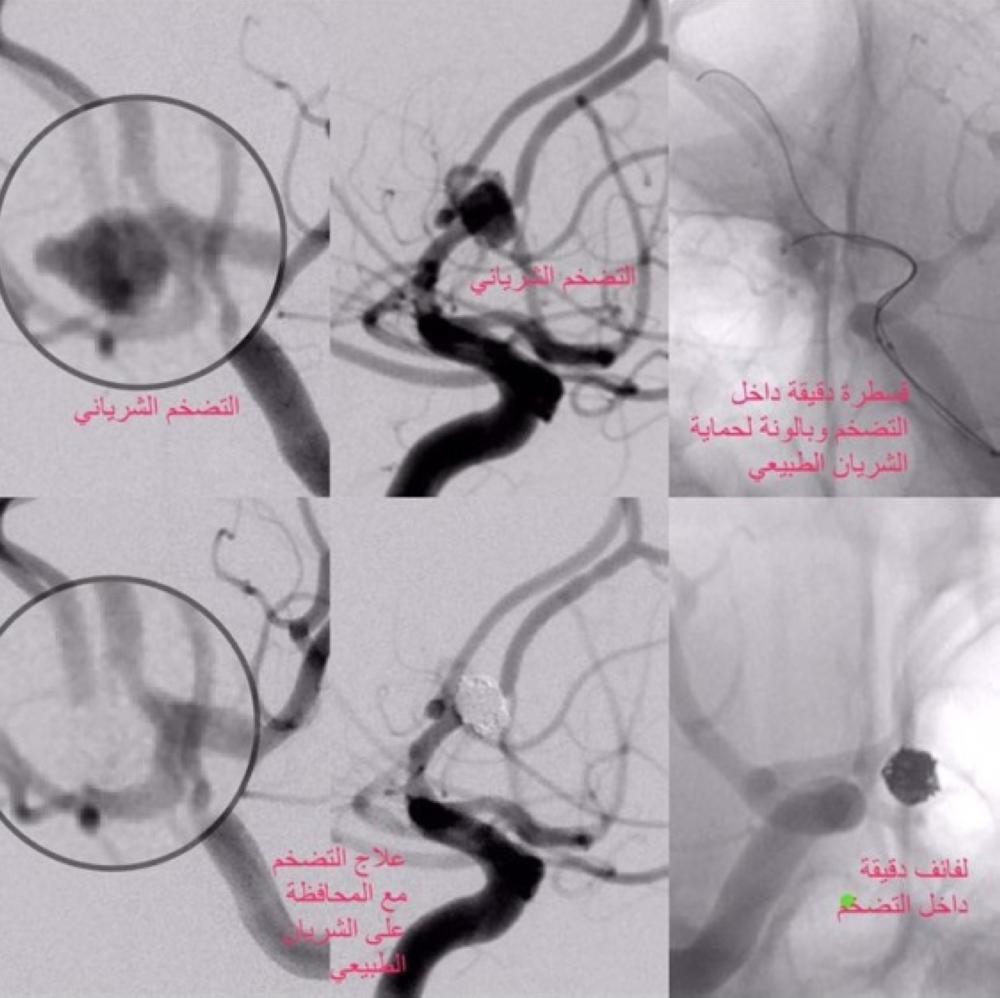

نجح فريق طبي متكامل من قسم جراحة المخ والأعصاب وقسم الأشعة التداخلية بمدينة الملك عبدالله الطبية بالعاصمة المقدسة، في إنقاذ حياة معتمرة ستينية أصيبت بغيبوبة مؤقتة وصداع شديد أظهرت فحوصاته الأولية إصابتها بنزيف دماغي من الدرجة الثانية نتيجة تضخم شرياني لا يتعدى حجمه أربعة ملليمترات.

وأوضح استشاري القسطرة الدماغية الدكتور فيصل الغامدي أنه تقرر إجراء العملية باستخدام قسطرة لعلاج التضخم الشرياني بمشاركة فريق الأشعة التداخلية وفريق تخدير الأعصاب، حيث تم استخدام قسطرة لا يتعدى قطرها نصف ملليمتر للوصول للتضخم الشرياني، ومن ثم تم علاجه بنجاح بلفائف خاصة لمثل هذا النوع من الحالات وتماثلت المريضة للشفاء في قسم العناية المركزة العصبية وخرجت من المستشفى لتلتحق ببعثتها ولله الحمد والمنة.